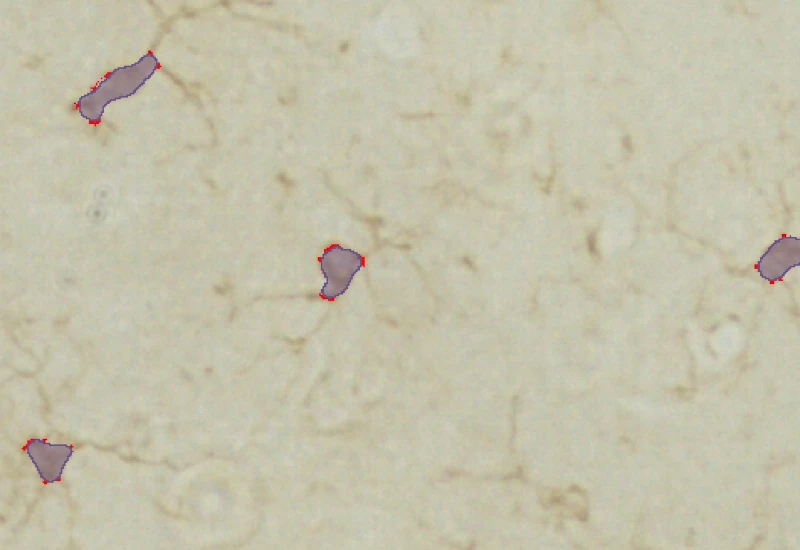

The IHC Microglia App detects microglia soma based on a specifc staining and further identifies branches as well as primary and secondary branching points. It outputs number and area of cells, number of primary and secondary branching points as well as area and lenght of the detected branches.

Soma detection

Microglia detection